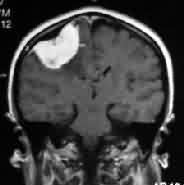

Falx meningioma-MRI